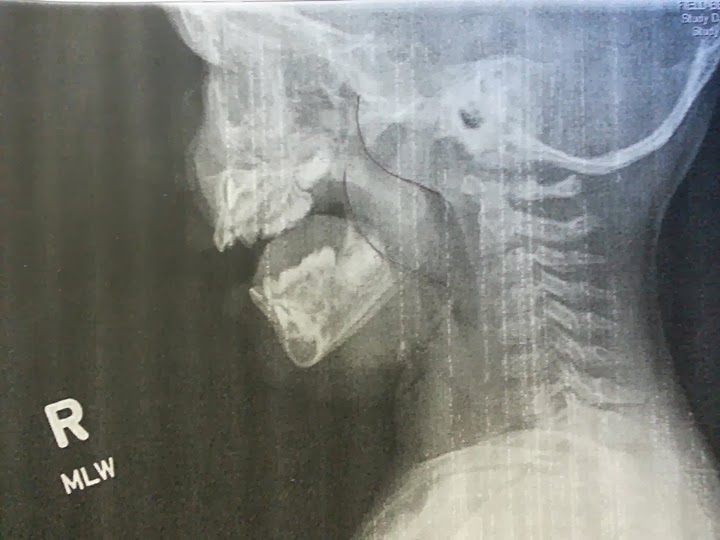

Fast forward to a couple of months ago. We had the docs look to see how the tubes were doing, one was out of the ear canal the other in place. A week later…ear infection. A couple weeks after run of antibiotics, another…repeat four times. In for a consult at Children’s and they confirmed that she needs a new set of tubes and additionally her adnoids and possibly her tonsils removed.

If she has to have her tonsils out, she will have to spend the night in the hospital.